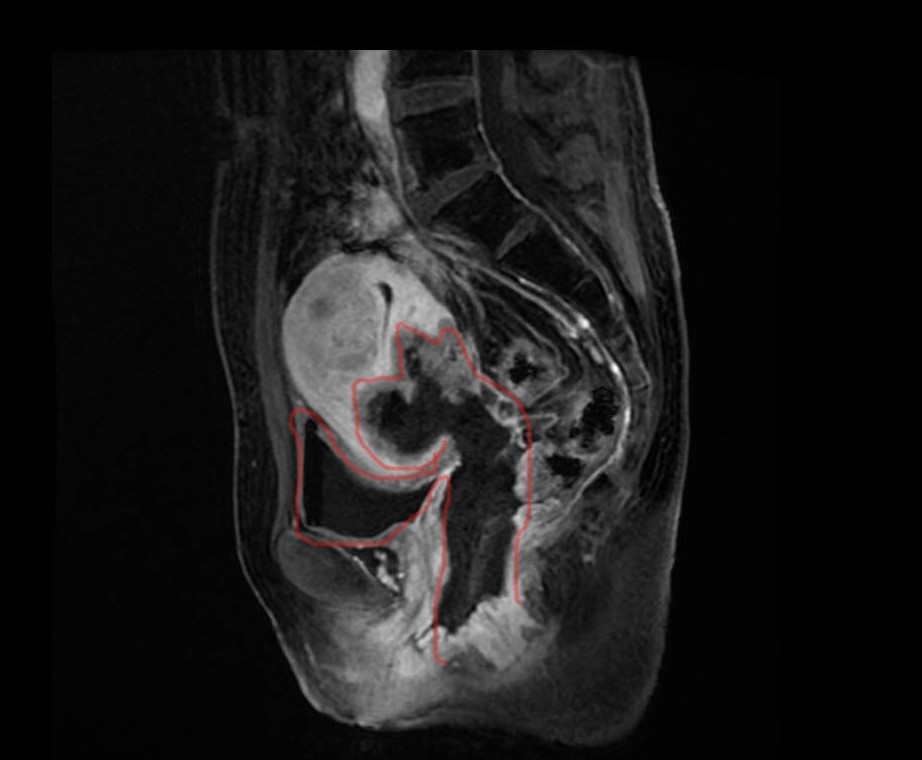

“全盆脏器切除术”是什么? 名字大家虽陌生,但多年来 却是盆腔晚期癌肿侵犯多器官患者的“福音” 近日,我院结直肠外科三区/放射性肠病专科、泌尿外科进行的多学科协作,进行“腹腔镜下全盆腔脏器切除手术”,堪称冲顶珠穆朗玛峰! 手术历时9.6个小时,出血仅150毫升,成功切除了一位年轻的宫颈癌治疗后复发合并严重放射性直肠-膀胱-阴道瘘患者的“责任病灶”,实现术前精准评测、术中出血量少、术后恢复快速,给患者迎来新生。 据结直肠外科三区/放射性肠病专科马腾辉医生介绍,该手术可实现严重放射性损伤及肿瘤复发病灶的“根治性切除”,对已被病情影响的所有及相关的邻近组织进行微创切除,并且,还可以同时满足患者日常排泄的生活需要,在下腹壁做尿、粪排泄双造口,可以极大程度缓解病情带来的不适感。 这种高效的治疗方案未被国内外攻克并普及是因为手术难度极高、时间很长、创伤较大。 据文献显示:全盆脏器切除平均手术时长逾10小时,术中出血量动辄超过1000 ml,术后并发症发生率可高达32%~84%,术后30天病死率可高达8.7%,为腹部外科、盆腔外科手术难度之最,此次我院在严重放射性盆腔损伤领域所采取的的腔镜下全盆脏器切除更是全盆切除手术中的难度之最。 马腾辉指出,在盆腔放射性损伤领域,既往不少外科医生顾及高剂量放疗后的盆腔慢性纤维化甚至“冰冻骨盆”等问题,对盆腔“责任病灶”(直肠瘘、膀胱瘘或癌肿)切除往往望而却步,提倡行单纯造口转流手术等姑息性治疗手段,无法实现病情的高效缓解。 另外,盆腔放射性损伤导致的最严重晚期并发症——放射性直肠膀胱阴道瘘行全盆腔脏器切除手术者,国内外更是鲜有治疗经验报道。 作为国内较早关注盆腔放射性损伤治疗的中心,截至今日,我院结直肠外科三区/放射性肠病专科联合泌尿外科已成功开展该类手术9例,并取得良好的疗效,不仅为患者带来“新的希望”,同时刷新相关医学领域的“经验盲区”。 这一次接受“最难外科手术”的患者是来自福建的陶女士。1年前,45岁的她不幸诊断为“宫颈癌”,她前期进行了常规的放化疗和免疫治疗,本以为痛苦就此终结。 然而,近2个月,她开始反复出现阴道排粪尿并伴肛门疼痛导致无法坐立与行走,这严重的影响了正常生活。 陶女士用“睁开眼第一秒都是疼痛,闭上眼每一秒都是噩梦”来形容这般痛不欲生的煎熬和精神折磨。 辗转于国内多家医院诊治后,陶女士检查出“直肠-膀胱-阴道瘘伴妇科肿瘤局部复发”,随着病情的加剧,各种药物止痛无效。 据了解,此类疾病的治疗较为棘手,患者通常伴有顽固性漏尿漏粪、严重的感染及疼痛,止痛药缓解有限,长期的心理负担会导致精神抑郁。排便困难导致畏惧进食,继而出现营养不良、恶病质,形成恶性循环。患者身心俱疲,苦不堪言。 基于目前国内专业化诊治放射性损伤的医院较少且该类手术难度极大,国内外多数医生均束手无策。陶女士经多番咨询后,慕名前来我院放射性肠病专科就诊。 ▲术前的MRI片显示:直肠与子宫、阴道融合,呈巨大空腔并与膀胱相通 基于陶女士病情的特殊性,我院专家会诊后一致认为:多轮药物治疗均收效甚微,如果“责任病灶”不切除,只能是姑息治疗尽量延长生存。 “我希望这次治疗可以彻底缓解我的疼痛”陶女士向结直肠外科三区王辉主任、马腾辉团队提出了自己的治疗诉求。 专业评估后,团队建议进行手术切除,这也是获得长期存活的唯一希望。 经过多学科评估以及多模式预康复管理的术前准备后,12月底,我院结直肠外科三区/放射性肠病专科的王辉、马腾辉团队与泌尿外科的邱剑光、王德娟团队强强联合,进行了“腹腔镜下全盆腔脏器切除手术”,历时9.6个小时,出血仅150毫升,完整切除了病变直肠、乙状结肠、膀胱、子宫、宫颈、阴道及受累的小肠、阑尾,并完成回肠代膀胱,降结肠经肛管拖出吻合(PE-Bacon手术)及预防性横结肠造口。 手术持续时间虽久,但由于使用了“腹腔镜技术”,创口小,术中出血量非常少。 “责任病灶”切除后,陶女士术后的疼痛症状明显缓解,并且可以很快下床活动并恢复进食,疼痛评分(NRS)也由术前的9~10分下降至术后1分。 术后第9天顺利完成“肛门成形术”,更好的缓解了肛门不适症状,为今后经肛排便争取了机会。 经过术后16天的精心治疗,陶女士顺利出院。 “手术后,疼痛好多了,生活质量极大的提升了”她开心地说。 目前已基本上可以正常饮食,心理负担大大降低,之前阴道漏尿漏粪的症状也没有了,也不需要依赖止痛药物,腹壁尿、粪双造口排泄功能也正常,病情大有好转。 期待半年后,陶女士返院复查,若评估恢复良好,将有机会实施关瘘手术并恢复经肛门排便功能。 多年来,在结直肠肛门外科三区、放射性肠病专科已故学科带头人、国家道德模范提名奖王磊教授的带领下和传承中,科室积累了国内最丰富的放射性肠损伤诊治经验。科室先后牵头制定了首部《中国放射性放射性直肠炎诊治专家共识(2018版)》及《中国放射性直肠损伤多学科诊治专家共识(2021版)》,并于2021年11月牵头全国多中心多学科专家成立了“中国放射性肠损伤研究协作组”。 持续致力于临床及医学前沿理论,为患者带来更安全、更精准、更高效的治疗方案。